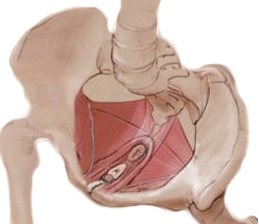

Ele reúne músculos, nervos e tecidos conjuntivos que formam o assoalho pélvico.

Aqui está o detalhe: essa rede sustenta órgãos como bexiga, útero e reto com precisão.

Imagine uma rede de segurança que evita prolapsos e mantém tudo no lugar.

Os músculos do períneo são um grupo complexo, incluindo o elevador do ânus e o isquiocavernoso, entre outros. Eles formam uma rede forte que sustenta os órgãos e permite o controle voluntário.

A base da pelve, onde o períneo se insere, é como os alicerces de uma casa. Uma base forte garante que toda a estrutura acima fique segura e estável. É ali que os órgãos encontram seu ponto de apoio.

A estrutura da base da pelve é composta por ossos, ligamentos e, claro, os músculos do assoalho pélvico. Qualquer fragilidade nessa base pode comprometer a saúde pélvica como um todo.